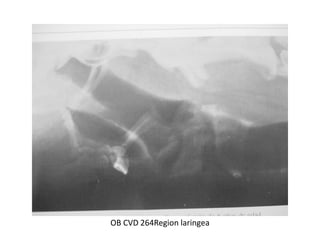

RADIOLOGIA DE CUELLO

OSCAR BENAVIDES

OB CVD 264Region laringea